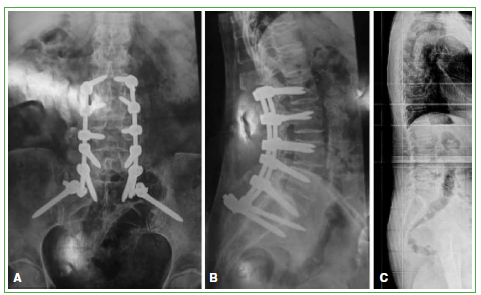

Figura 2. A y B.

Radiografías que muestran instrumentación en L2-pelvis que empeoró el cuadro de síndrome de la espalda inclinada y de dolor lumbar. C. Radiografía tras la retirada del material.